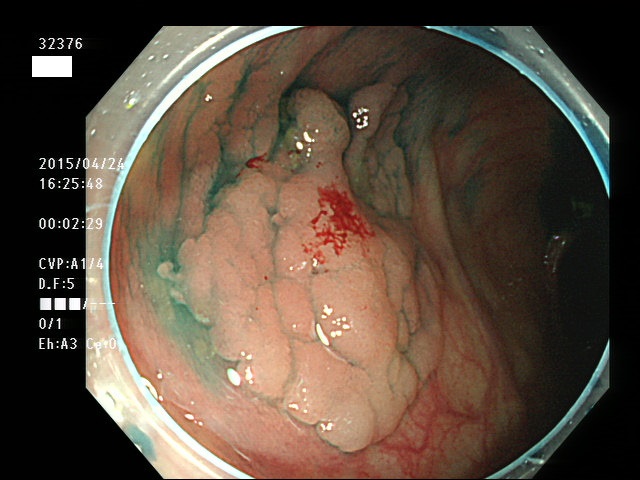

上記100名より抽出した平坦・陥凹型腺腫(=癌化の危険が高いが見落としやすい病変)の内視鏡写真

32354 32357 32359 32362 32363 32364 32365 32366(SSA/Pのみ) 32368 32369 32370 32371 32372 32373 32374 32375 32376 32378 32379 32380(SSA/Pのみ) 32381 32382 32383 32384 32385 32386 32388 32389(SSA/Pのみ) 32390 32391(SSA/Pのみ) 32392 32395 32396 32397 32398